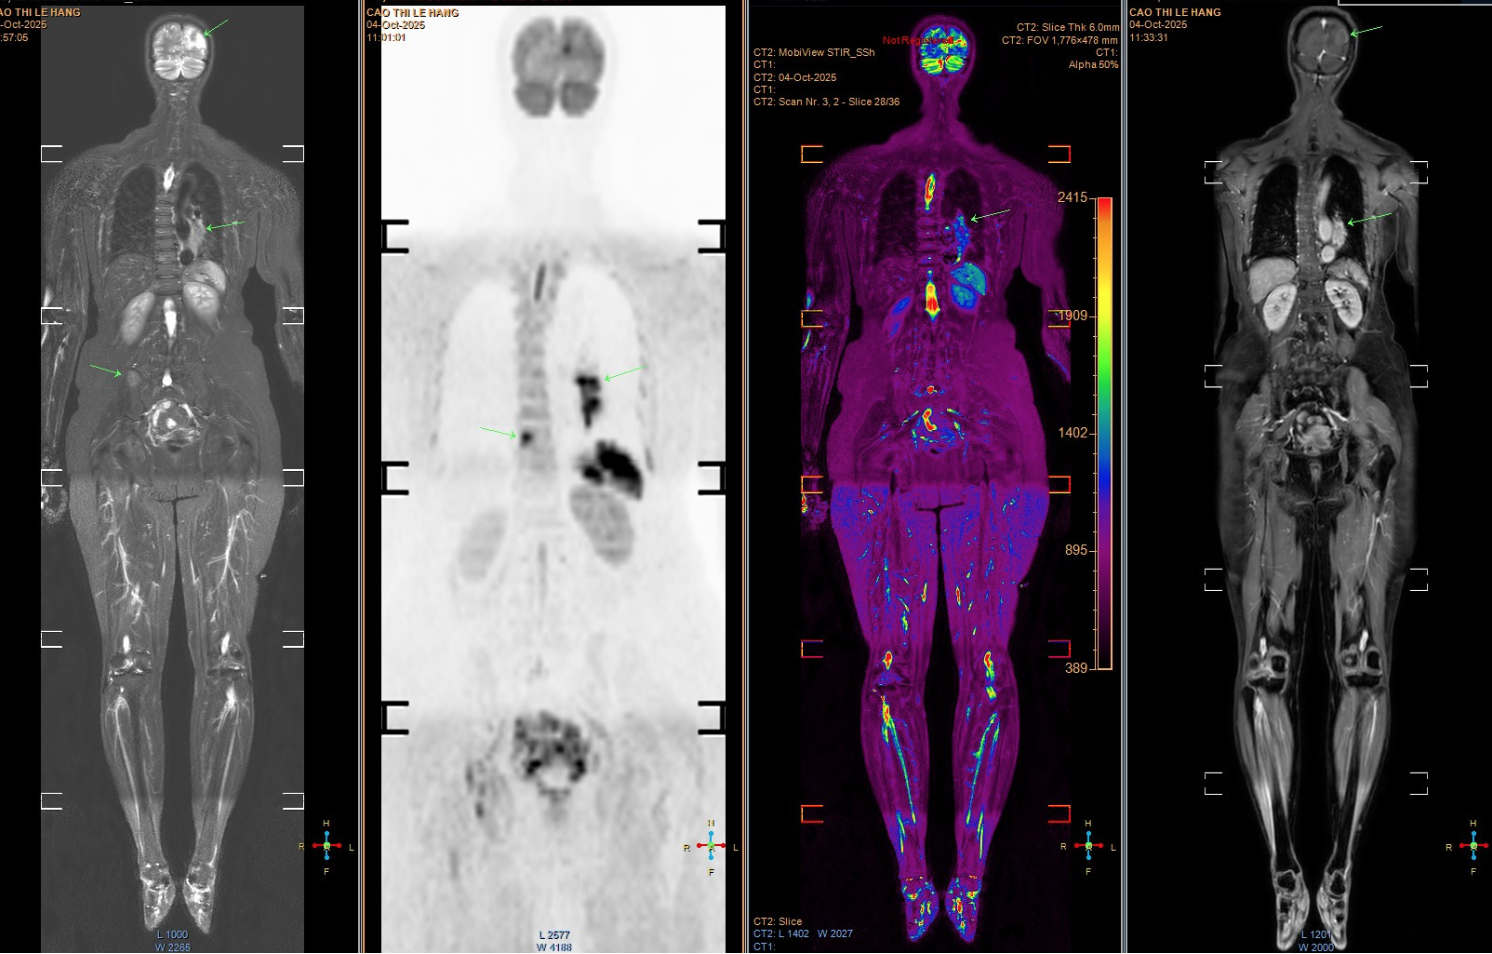

Mắc ung thư giai đoạn cuối di căn não, người phụ nữ đi khám, òa khóc khi biết “thủ phạm” đến từ chồng con- Ảnh 1.

Hình ảnh chụp tổn thương di căn của bệnh nhân. (Ảnh: Bác sĩ cung cấp)